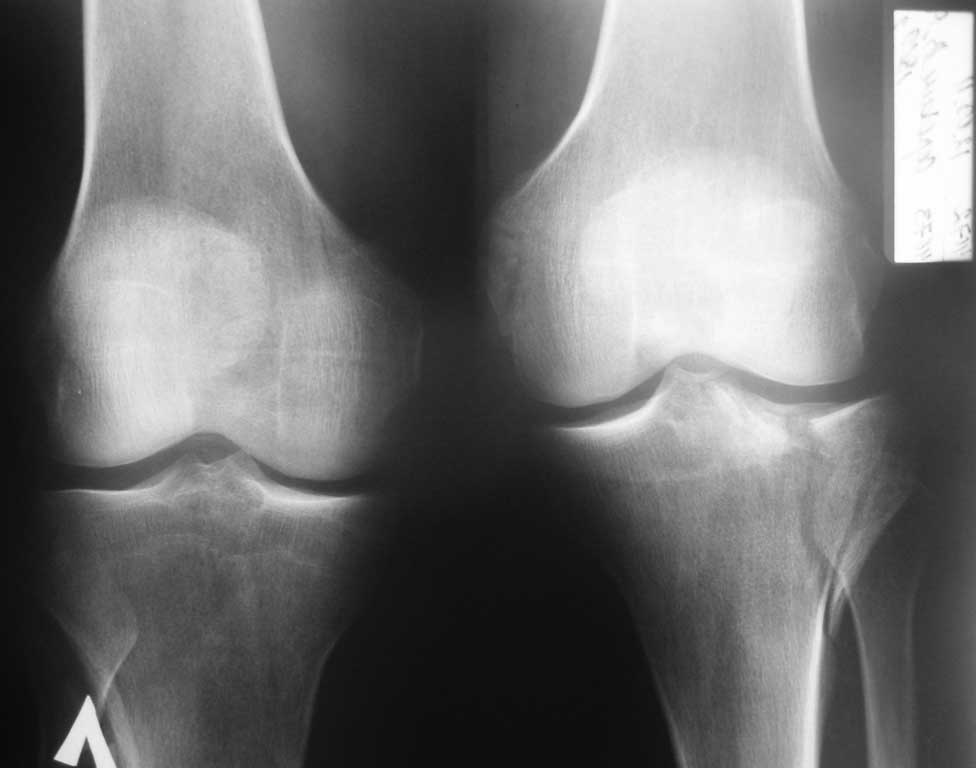

с данным переломом, в условиях отсутствия артроскопии и "Т" и "L"-образных пластин. Травма в результате ДТП, 41 год, пост геморрагическая анемия, перелом тибиального плато, В1. Имеются в наличии только спонгиозные шурупы ( смешно конечно и горько). Хотелось бы уточнить, стоит ли делать артротомию для репозиции, или попытаться закрыто фиксировать перелом?